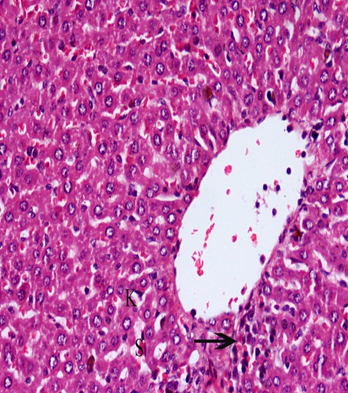

Normal structure of the hepatocytes, central vein, sinusoidal spaces and prominent nucleus were observed in the liver section of control rats (fig. 2). Cisplatin exposure caused marked damage to hepatocytes in the form of degeneration, cytoplasmic vacuolation, centrilobular necrosis associated with mononuclear cells infiltration around central vein and the central vein was enlarged and congested. The sinusoid walls showed numerous Kupffer cells, hemorrhages with sinusoids dilatation, and nuclei are pyknotic with condensed chromatin (fig. 3).

Fig. 2: It shows photomicrograph of section from liver of control group

Fig. 3: It shows photomicrograph of section from liver of cisplatin (H and E X 400)

In the group received ginger and carrier showed nearly normal structure with few Kupffer cells and hemorrhage blood sinusoids (fig. 4 and 5).

Fig. 4: It shows photomicrograph of section from liver of Carrier group (H and E X 400)